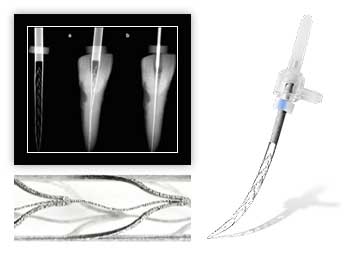

Восстановление зуба пломбировочным материалом, с использованием анкерных штифтов, жевательного

13320

Восстановление зуба пломбировочным материалом, с использованием анкерных штифтов, фронтального

16147

Восстановление зуба пломбировочным материалом, с использованием стекловолоконного штифта, жевательного

14066

-

Восстановление зуба пломбировочным материалом, с использованием стекловолоконного штифта, фронтального

14924